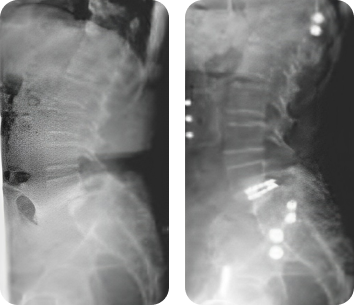

Клинический пример

Применение кейджей VariAn ExpandableTM при хирургическом лечении спондилолистеза и сколиотической деформации.

- Пациент:

- Женщина, 51 год.

- Диагноз:

- Дегенеративный спондилолистез поясничного отдела позвоночника со стенозом позвоночного канала.

- Лечение:

- Выполнена редукция и фиксация кейдами VariAn ExpandableTM. Контрольные рентгенограммы выполнены через 1 и 2 года после операции.